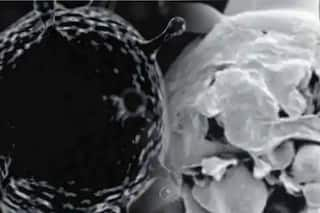

दिल्ली के सर गंगाराम अस्पताल में व्हाइट फंगस के कारण कोविड-19 के मरीज की पूरी आंत में अनेक छेद होने का अपनी तरह का पहला मामला सामने आया है.

दिल्ली में व्हाइट फंगस का एक ऐसा मामला सामने आया है जिसमें मरीज की छोटी आंत और बड़ी आंत में छेद हो गया है. सर गंगाराम अस्पताल में यह मामला मिला है.